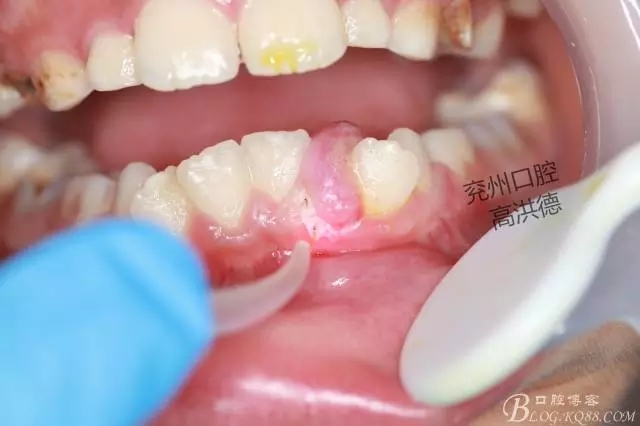

口內(nèi)觀

囑患者常規(guī)口服抗生素,保持口腔衛(wèi)生,一周后復(fù)診。